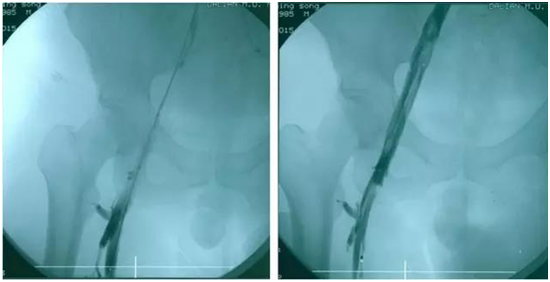

病情危重;难点在于下腔静脉滤器置入术通常是从右侧

深静脉血栓(DVT)形成发生率有上升的趋势。下腔静脉滤器(inferior caval filtration)置入术的目的是阻拦和捕捉源于下肢的游离血栓,预防PE(PE)[1]。然而我们在考虑置入滤器时,必须切记滤器不能预防下肢DVT,也不能提高药物治疗DVT的疗效[2]。为此我们需要熟悉下腔静脉滤器置入术的指征和利弊。 1 腔静脉滤器的选择 早期使用的滤器为Mobin-Ubbin伞式滤器,目前广泛应用的滤器包括Greenfield滤器、Vena Tech滤器、Bird's-Nest滤器、Simon Nitinol滤器等,而以各种改良的Greenfield滤器应用最普遍[3-7]。按使用方法,分为永久性滤器、临时性滤器和可回收性滤器。 永久性滤器置入体内后长期存放,理论上不需要取出。实际上滤器置入久了,会出现很多并发症(移位、下腔静脉阻塞等),失去其应有的价值。临时性滤器用于短期置入,一般在10-15天后取出,缺点是难以达到DVT治疗的目的。可回收滤器可以不借助连接装置而自身稳定于下腔静脉,目前的"可回收"时间窗只能在滤器与静脉壁连接处完全上皮化后很短时间内才能实现

下腔静脉滤器安放步骤下腔静脉滤器安放步骤下腔静脉滤器安放步骤下腔静脉滤器安放步骤 (2006-09-21 23:22:18) 1.选取穿刺部位:对一侧髂股静脉血栓患者,取对侧(即健侧)股